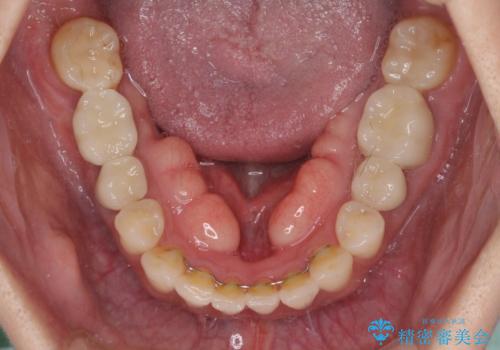

- 右下の欠損部の治療を希望して来院された患者様です。

部分矯正を行った後にインプラント埋入と手前の歯の根管治療を行い、その後補綴治療を行うこととしました。

治療途中より、上の歯や反対側の銀歯、上顎前歯の色合いや下顎前歯のデコボコが気になってきたため、全てを治療することとしました。